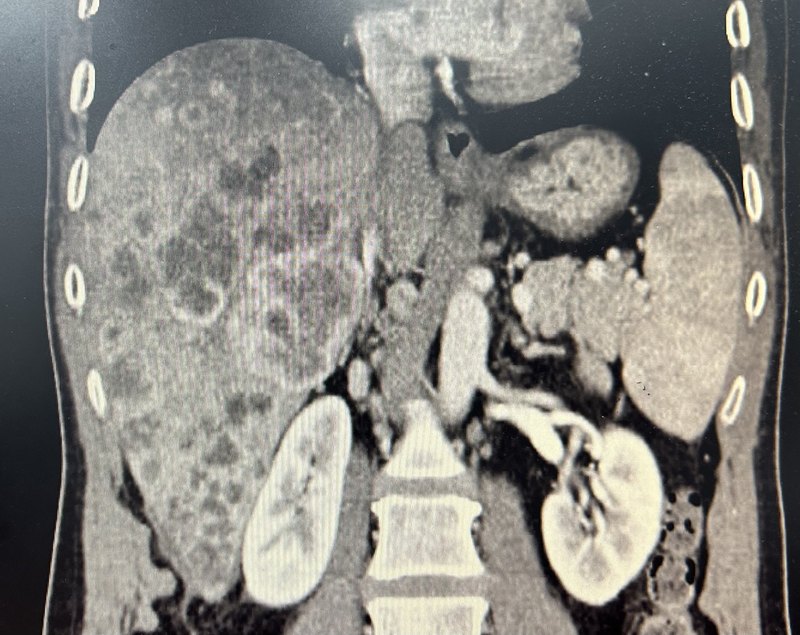

患者男性52歲,2023-11發(fā)現(xiàn)肝內(nèi)彌漫腫瘤并門脈右支癌栓并腹膜后可疑淋巴結(jié)轉(zhuǎn)移,外科評(píng)估無(wú)手術(shù)指征。11-15在我科行CT下穿刺活檢加TACE+HAIC術(shù)。造影見(jiàn)腫瘤染色明顯,采取恒瑞100-300um載藥微球栓塞部分腫瘤后保留導(dǎo)管行灌注化療,奧沙利鉑100mg加亞葉酸鈣400mg加5-FU2.5g灌注24小時(shí)。ca199:1947U/ml,穿刺病理提示肝內(nèi)膽管癌。并口服國(guó)產(chǎn)侖伐替尼8mg每天,并每月注射替雷麗珠單抗200mg。2023-12,2024-1,2024-2,再次行TACE+HAIC方案基本同前?;颊遚a199逐漸下降,從1947U/ml~ca199:487U/ml~ca199:211U/ml~ca199:102U/ml。2024-4行肝腫瘤微波消融治療。肝腫瘤微波消融治療,術(shù)后ca199:100U/ml,無(wú)明顯下降。復(fù)查CT見(jiàn)肝內(nèi)腫瘤基本壞死。外科評(píng)估可行姑息性腫瘤切除。2024-5行肝腫瘤切除加淋巴結(jié)清掃。術(shù)后肝內(nèi)未見(jiàn)殘余腫瘤繼續(xù)密切隨診。介入手術(shù):深圳市人民醫(yī)院介入科吳宇旋主任醫(yī)師陳現(xiàn)現(xiàn)主治醫(yī)師團(tuán)隊(duì)外科手術(shù):深圳市寶安區(qū)中心醫(yī)院邱振雄主任團(tuán)隊(duì)。點(diǎn)評(píng):初診失去手術(shù)指征的肝內(nèi)膽管癌預(yù)后差,以往介入治療效果也不滿意,我們近期采取載藥微球加灌注化療的方案局部效果顯著,再聯(lián)合靶免治療加強(qiáng)治療效果,本案例目前為止效果滿意,且成功轉(zhuǎn)化手術(shù)。但患者已經(jīng)有淋巴結(jié)轉(zhuǎn)移,最后能否獲得滿意生存期仍然有待觀察。為減少灌注化療的全身反應(yīng),我們采取部分栓塞加部分化療的方案,盡量減少化療藥的量,適當(dāng)延長(zhǎng)化療間隔,灌注時(shí)間也盡量控制24小時(shí)內(nèi),盡量減少患者長(zhǎng)時(shí)間臥床的痛苦。這個(gè)方案為無(wú)手術(shù)指征的肝內(nèi)膽管癌提供一定的參考意義,但是否位為最佳方案仍然有待驗(yàn)證。補(bǔ)記:患者術(shù)后ca199已經(jīng)下降到正常,繼續(xù)系統(tǒng)治療鞏固療效。